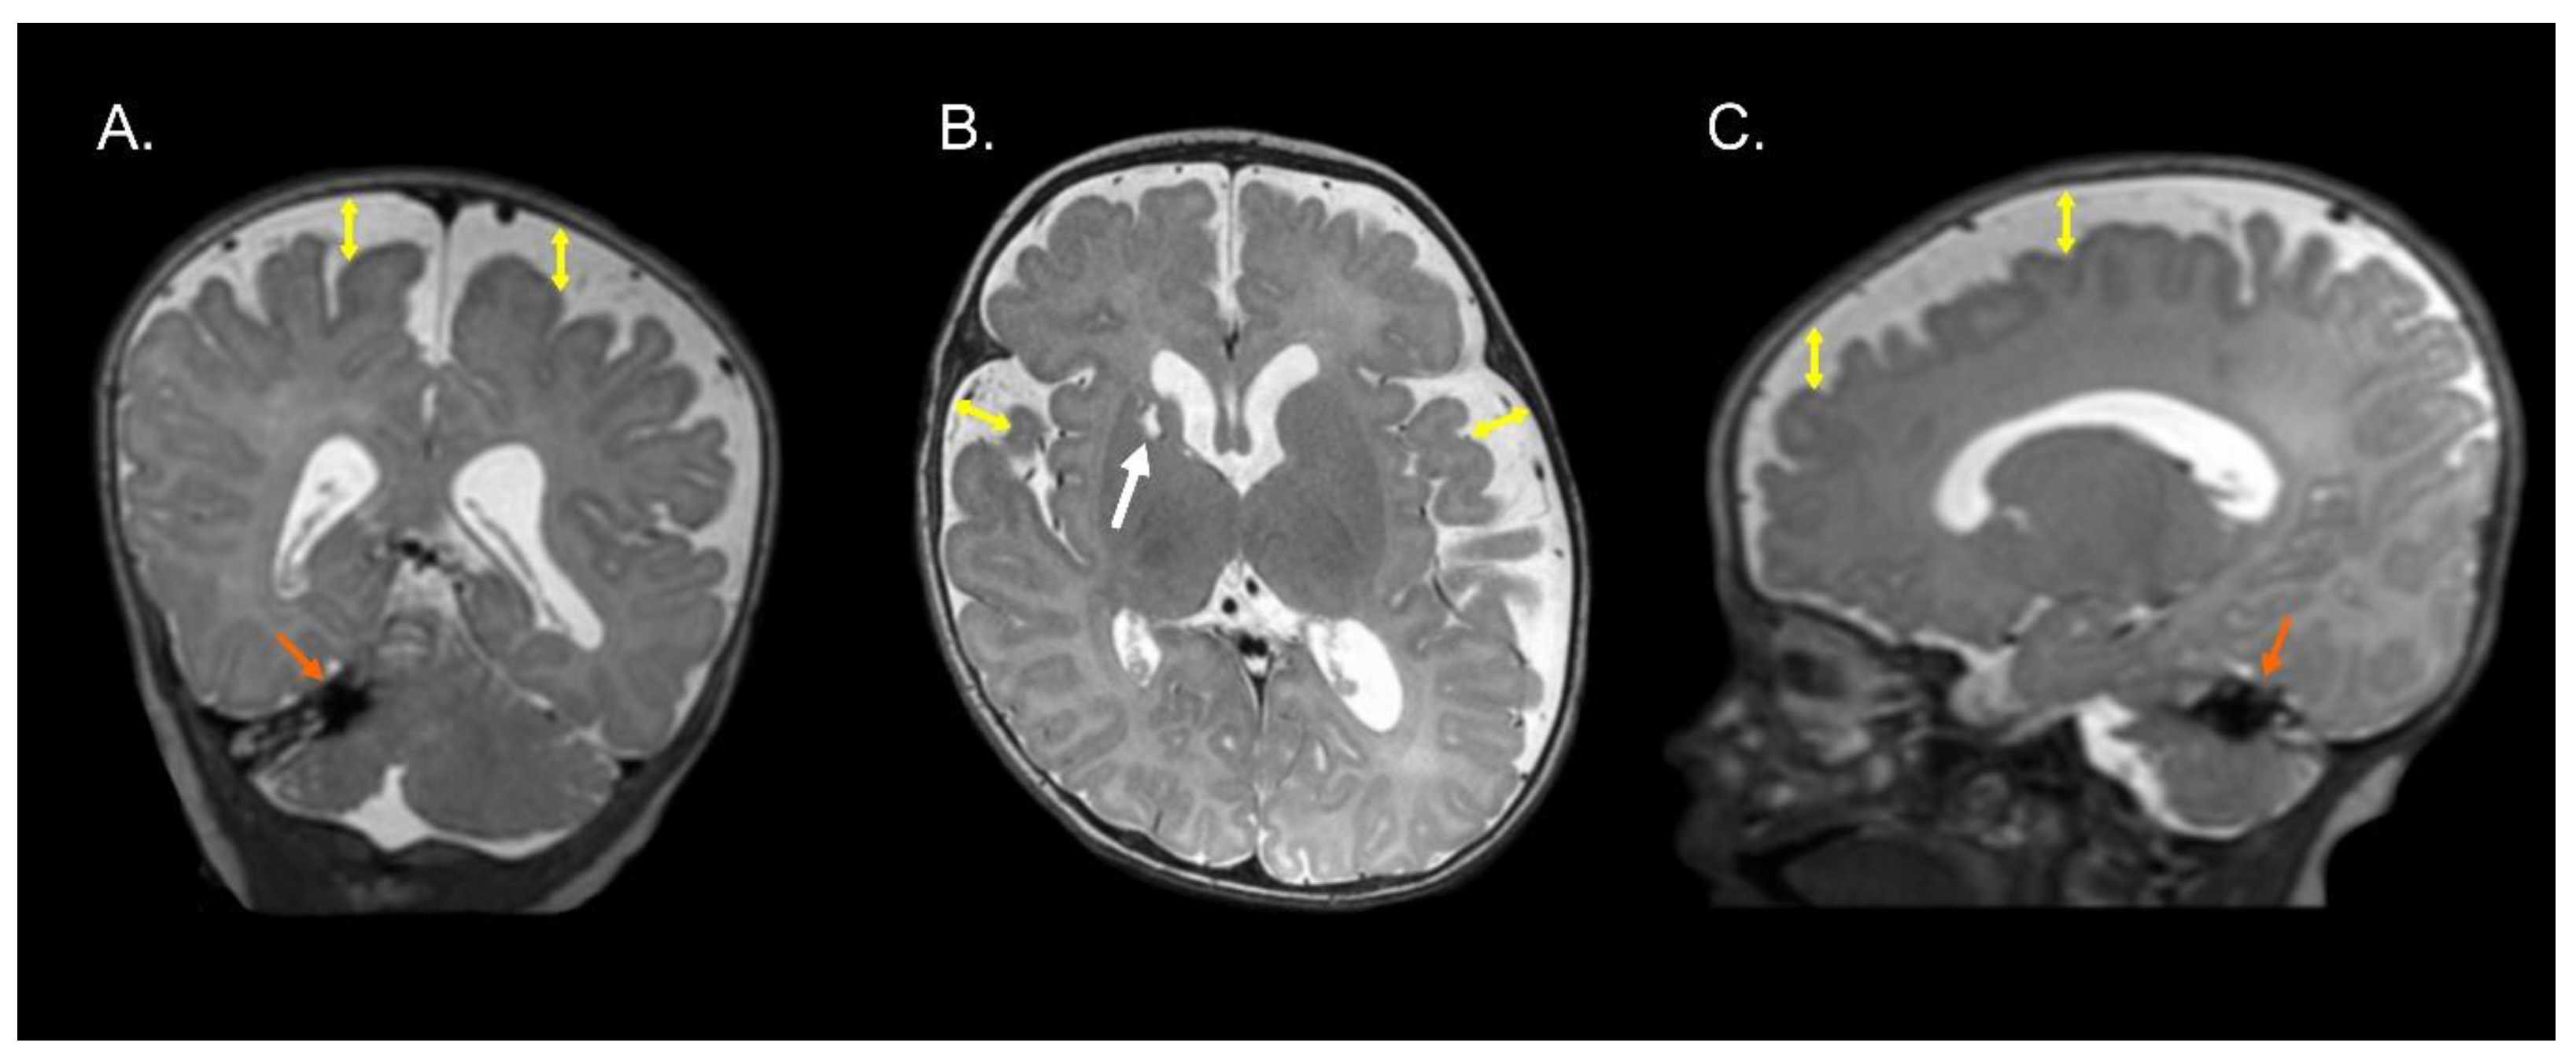

Figure 1, Figure 2 and Figure 3 show the MRI of three infants at the beginning of Katona’s treatment.

Figure 1.

Coronal (A), axial (B), and sagittal (C) T2-weighted structural MRI of a preterm infant (born at 34 gestational weeks) at 2 months of corrected age with right cerebellar hemorrhage (orange arrows) and ischemic process with cystic degeneration in head of right caudate nucleus (white arrow). Note an enlargement of the lateral ventricles (left predominance) and increase in the subarachnoid space in the fronto-temporo-parietal region (double headed yellow arrows). Images in radiological convention.